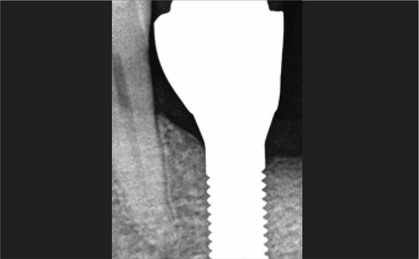

Bild  10:

Kontrollröntgenbild nach prothetischer Versorgung. Beachten Sie die stabilen marginalen Knochenverhältnisse.

Bild  13:

Kontrollröntgenbild von Position 36 zum Zeitpunkt der Implantation und zum Zeitpunkt der prothetischen Versorgung. Sehr stabile marginale Knochenverhältnisse.

Bild  14:

Das Patent™ Implantatsystem bietet mit dem Glasfaserstift eine große prothetische Flexibilität. Einzelelemente oder Brückenkonstruktionen können auf sehr effiziente Weise mit traditionellen zahntechnischen Methoden hergestellt werden.Das Implantatdesign ermöglicht eine vollständige Biointegration mit der rauen Oberfläche im Knochen und der bearbeiteten Oberfläche am transmukosalen Teil. In Kombination mit dem Design ohne Mikrospalt tief im Weichgewebe ergibt sich ein sehr stabiles Weichgewebeniveau, siehe Röntgenaufnahmen in den Bildern 3, 10, 14, 14. Das Patent™ Implantatsystem hat Überlebensraten gezeigt, die mit denen von Titan vergleichbar sind und zudem eine sehr positive Reaktion des Weichgewebes ergeben.